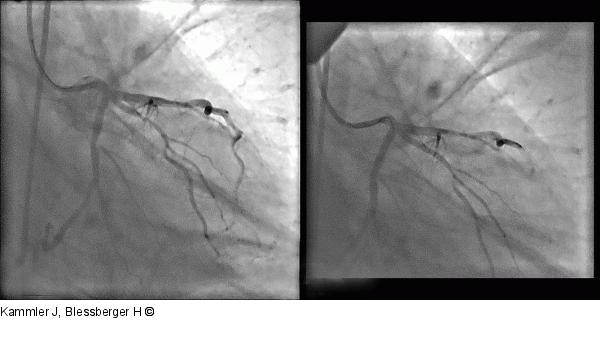

Abbildung 10: Angiogramm Angiogramm des Patienten 2: Stenose des Ramus obliquus vor (a) und nach (b) Intervention |

Angiogramm des Patienten 2: Stenose des Ramus obliquus vor (a) und nach (b) Intervention |